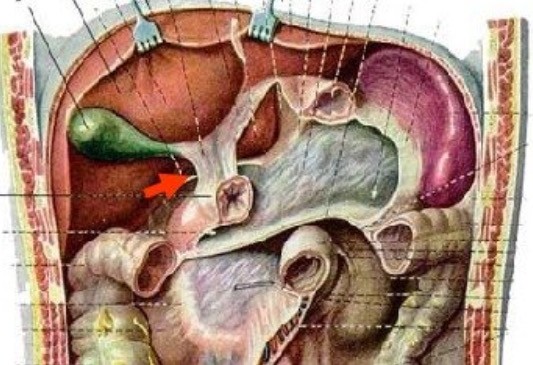

Анатомия и особенности Гартманова кармана желчного пузыря